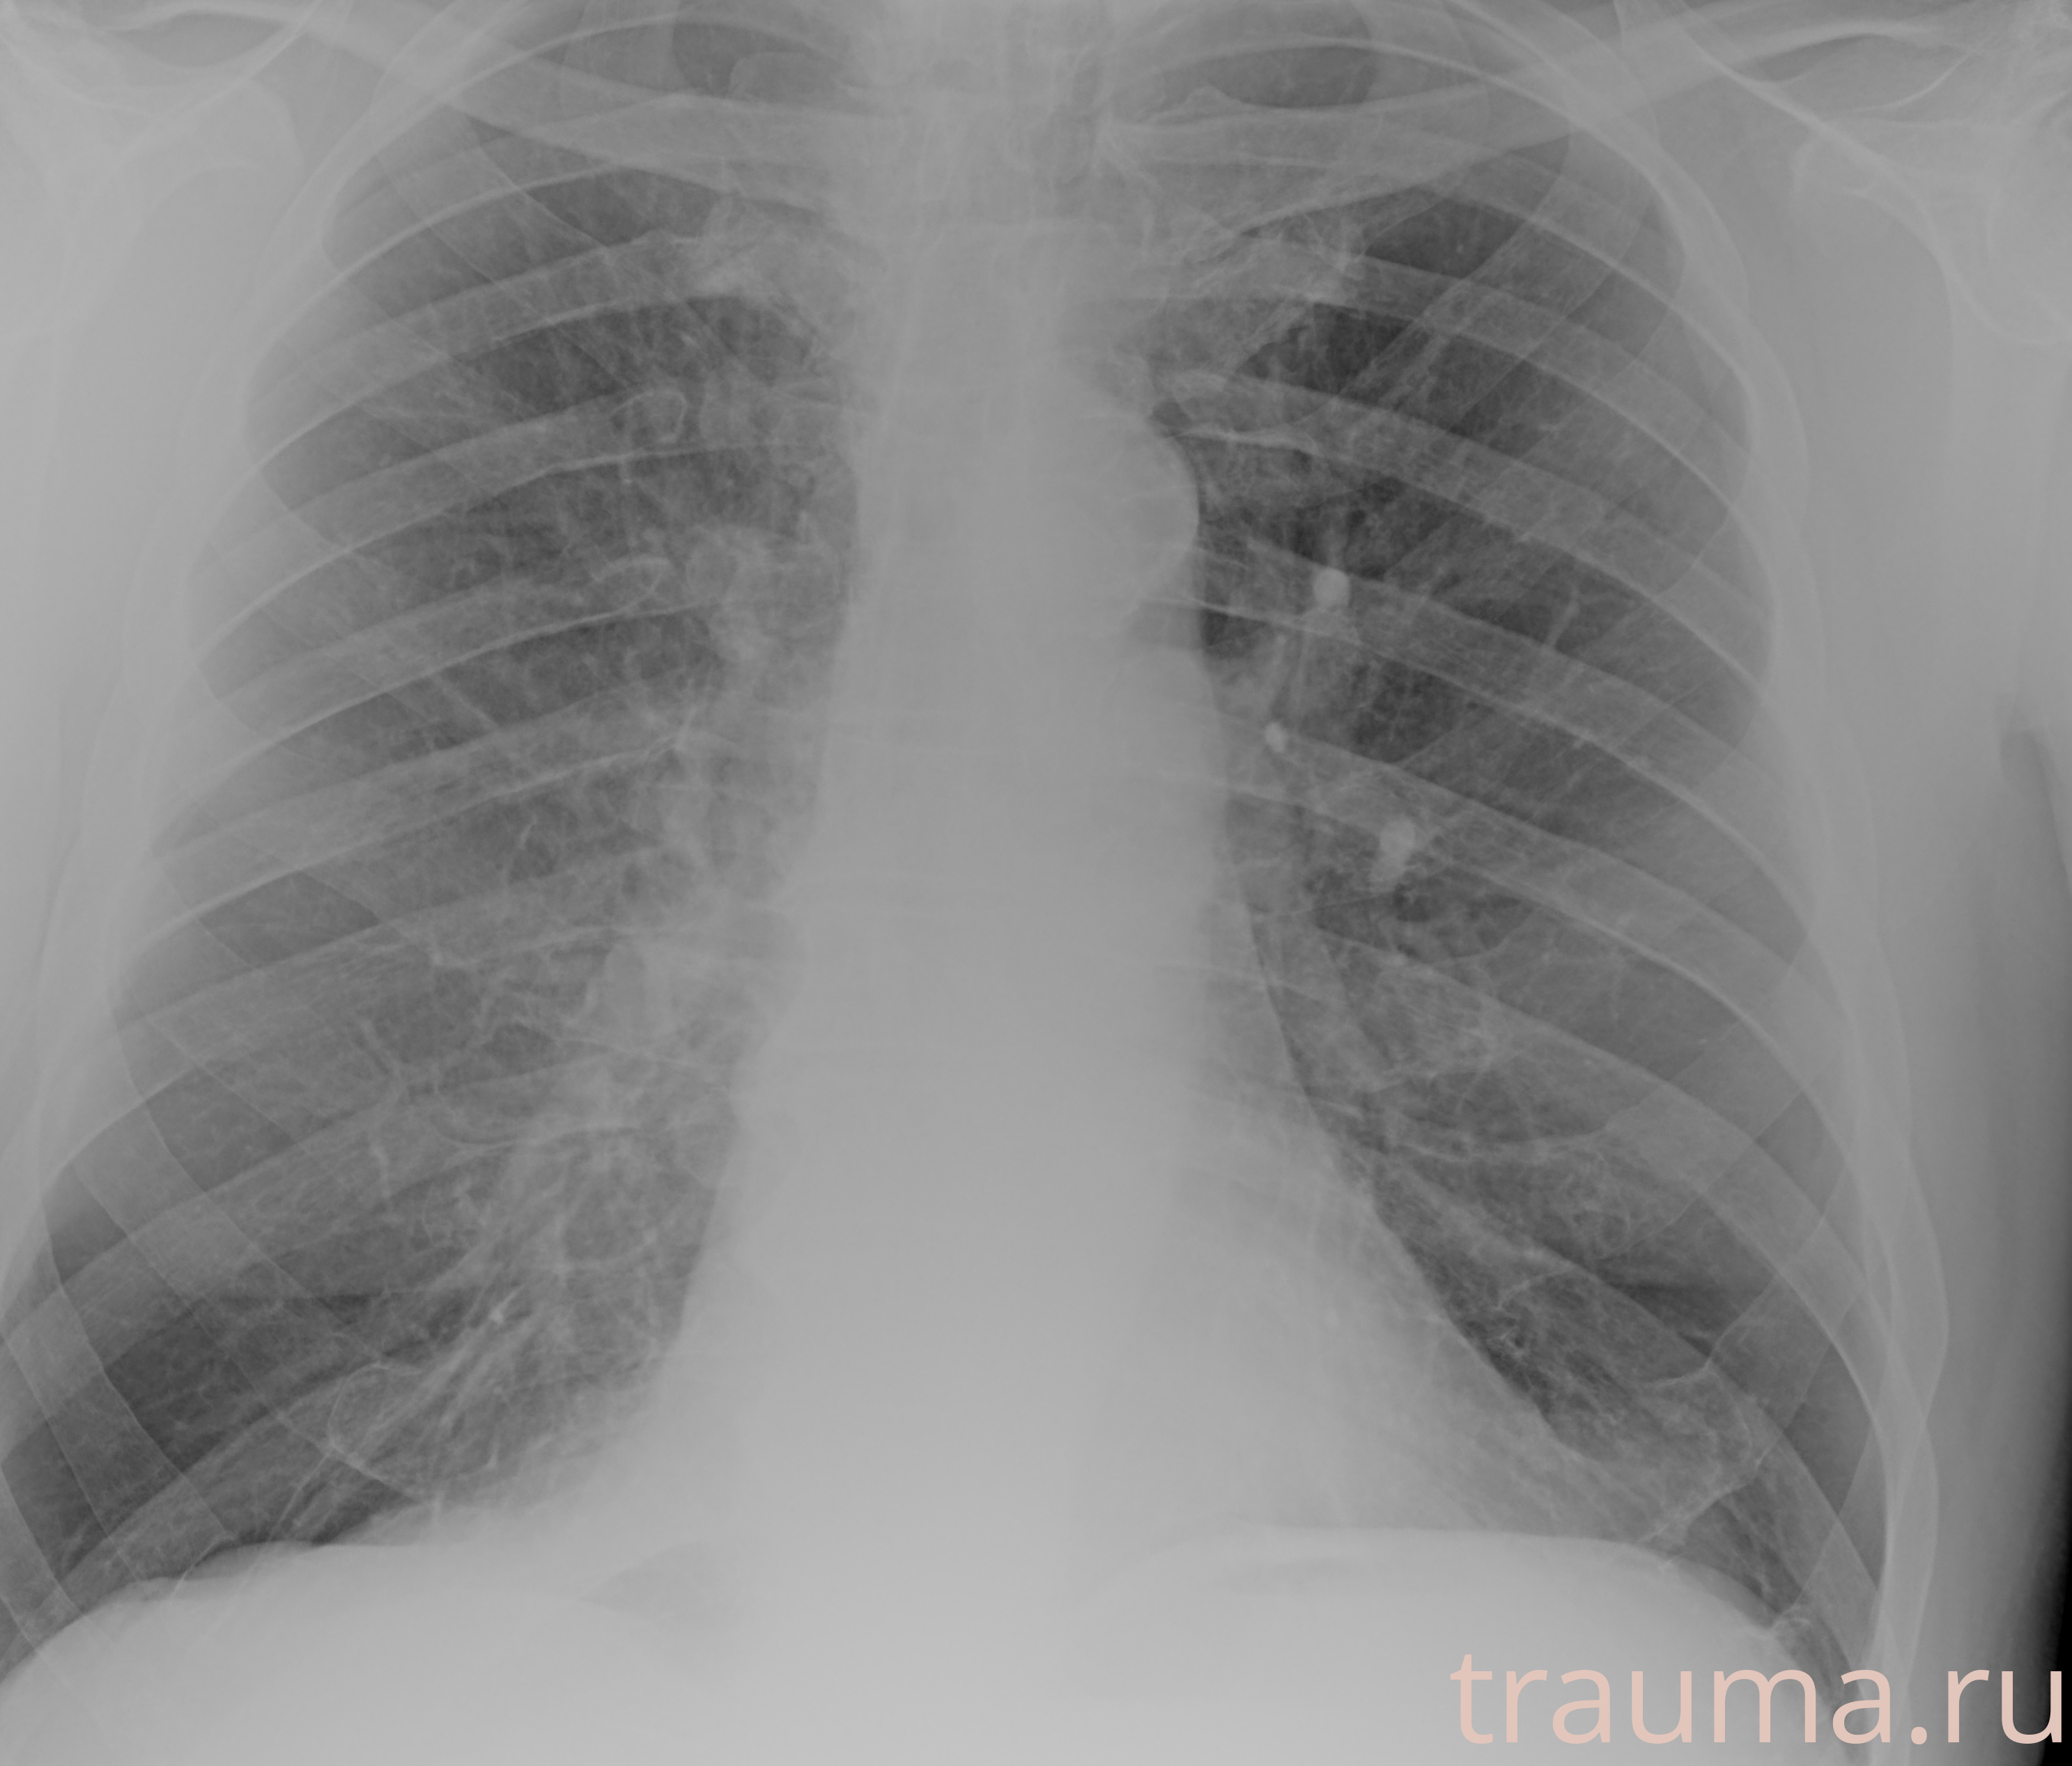

Рентгенограммы

Рентген на дому: по вашему адресу приезжает врач-рентгенолог, травматолог-ортопед с мобильным рентгеновским аппаратом, проводит диагностику травмы или заболевания, делает необходимые рентгенограммы, дает рекомендации по дальнейшему лечению. Получить качественные снимки в домашних условиях возможно благодаря уникальной методике, разработанной МосРентген Центром для института  Склифосовского

при переломе шейки бедра и пневмонии от компании МосРентген Центр - партнера Института имени Склифосовского